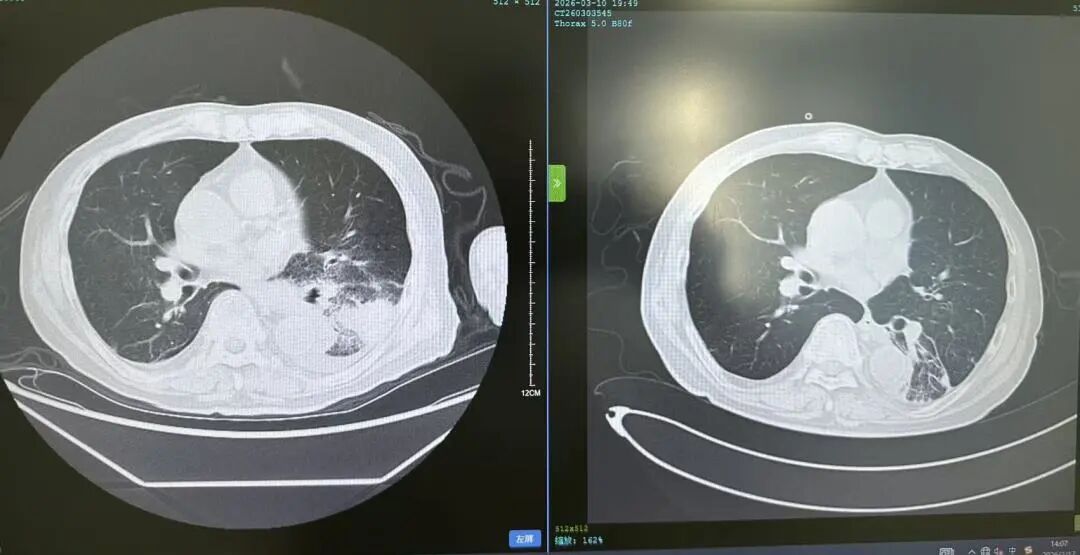

花鸟相伴本是生活雅趣,但鸟类羽毛碎屑、排泄物及粉尘中潜藏的有害物质,却可能悄然成为肺部健康的“隐形杀手”。这类疾病起病隐匿、症状不典型,极易被误诊或漏诊,严重时甚至可迅速进展为重症肺炎、呼吸衰竭,危及生命。近日,葫芦岛市第二人民医院呼吸与危重症医学科连续收治多例与接触鸟类密切相关的肺部疾病患者,为广大“养鸟一族”敲响警钟。 病例一:久咳不愈竟致呼吸衰竭 真凶竟是“养鸟过敏” 50岁的刘先生咳嗽、咳痰、气短两个月,严重时彻夜难眠,辗转求医无果,入院时已确诊I型呼吸衰竭。肺部影像学检查显示,双肺广泛存在磨玻璃影,局部已呈现“白肺”表现。此时,鉴别是感染性还是非感染性因素,成为诊断的关键。 ↑氧分压<60mmHg、二氧化碳氧分压正常、呼吸频率异常,呼吸衰竭 ↑相关检验项目正常,排除感染性因素 宋刚主任细致追问病史,发现其长期接触鸟类,结合支气管镜检查排除常见感染,最终明确诊断为外源性过敏性肺泡炎(过敏性肺炎),合并急性喘息性支气管炎。病因正是吸入鸟类羽毛及排泄物中的特异性蛋白过敏原,导致肺部过敏性炎症损伤。在脱离过敏原、接受经鼻高流量等规范治疗后,刘先生症状迅速缓解,顺利康复出院。 ↑左侧为治疗后肺部影像,右侧为治疗前肺部影像,肺炎明显减轻 病例二:高龄重症合并多重基础病 幕后黑手竟是鹦鹉热衣原体 86岁的杨大爷持续高热3天,体温达39℃,入院时已出现严重呼吸衰竭。更棘手的是,患者有20年再生障碍性贫血病史,白细胞、血小板极低,属典型免疫抑制,极易感染罕见病原菌。因血小板过低,行支气管镜检查出血风险极高。科室另辟蹊径,采用痰液NGS检测,精准锁定了致病元凶——鹦鹉热衣原体,这是一种经鸟类传播的非典型病原菌。 ↑鹦鹉热衣原体检测结果 ↑患者再生障碍性贫血,白细胞、血小板极低 诊断明确,治疗却面临两难:患者合并下肢静脉血栓,本应进行抗凝治疗,却因血小板严重低下受限。医疗团队综合研判、分层施策,严密监测血氧及肺栓塞风险,同步控制感染,并多次输注血小板、白蛋白及免疫球蛋白加强支持治疗。经综合救治,杨大爷病情好转,顺利出院。 ↑左侧为治疗前影像,右侧为治疗后影像,感染明显好转 病例三:体检发现肺部团块影 不是肺癌是真菌 患者养鸟多年,体检时发现右下肺团块状阴影,家属一度担心是肿瘤。但宋刚主任对比前年肺部影像,凭借丰富经验判断:恶性肿瘤在一年内长成如此大的团块相对少见,且病灶周围有典型晕征,高度怀疑是隐球菌肺炎——这是一种真菌性感染病,致病菌常寄生于鸟类粪便中。随后通过隐球菌荚膜多糖抗原检测,快速明确隐球菌肺炎诊断,规范抗真菌治疗后,病灶逐步缩小,病情控制稳定。 ↑隐球菌肺炎疗程较长,左侧为治疗后1个月的肺部影像,右侧为治疗前肺部影像,可见左侧晕征较右侧减轻 专家提醒:养鸟有风险 呼吸不适须警惕 宋刚主任表示,日常养鸟需做好防护: ☑ 注意环境卫生,保持通风干燥,控制粉尘; ☑ 定期清洁鸟笼与排泄物,清理时佩戴口罩、手套,避免直接接触; ☑ 老人、免疫低下、基础病较多者更需格外警惕。若出现长期咳嗽、气短、发热等症状,且有鸟类接触史,务必及时到专业呼吸科就诊,避免误诊漏诊。 我院呼吸与危重症医学科作为市级重点专科,致力于各类重症肺炎、呼吸衰竭、慢性气道疾病、哮喘等疾病的鉴别及规范化治疗,复杂疑难重症诊疗能力突出。同时携手中国医科大学附属第一医院,顶尖呼吸科专家每月定期来院出诊,让滨城百姓在家门口就能享受到省级优质医疗服务,为群众呼吸健康筑牢坚实屏障。 人民医院 人民名医 宋刚 主任医师 ·葫芦岛市第二人民医院呼吸与危重症医学科主任 ·辽宁省生命科学学会东北呼吸与危重症医学(PCCM)分会辽宁省基层委员会副主任委员 ·辽宁省细胞生物学学会放射粒子治疗专业委员会理事 ·辽宁省抗击新冠肺炎疫情先进个人 ·辽宁省预防医学会第一届吸烟相关疾病防治专业委员会委员 ·葫芦岛市劳动鉴定委员会专家库成员 ·葫芦岛市医学会呼吸内科学分会第三届委员会副主任委员 专业特色:擅长呼吸系统疑难及急危重患者的救治,如急慢性支气管炎、支气管哮喘、慢性阻塞性肺疾病、肺炎、肺栓塞、肺癌、间质性肺疾病、睡眠呼吸暂停综合征等,尤其擅长有创无创机械通气、支气管镜下相关检查及治疗(TBNA、气道支架置入术、球囊扩张等)、全肺灌洗术等领先技术,发表国家级期刊多篇。 出诊时间:每周二、周四全天 出诊地点:门诊二楼东侧35诊室 咨询热线:0429-8010115